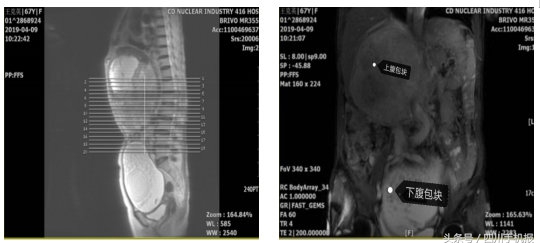

她的上腹右肋下、下腹盆腔内各有一处包块,大小分别约20cm、16cm,最大那个已经十分接近标准足球的大小。

这两个家伙在她的肚子里看似安分,但无时无刻不挤压着她的肠管、肝脏、胰腺、右肾等等器官。